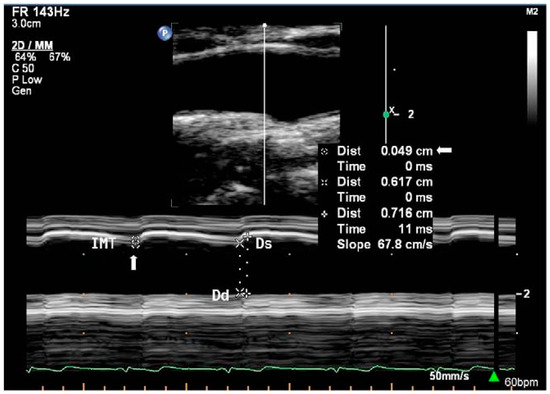

In area or diameter measurement, sound waves emitted by the transducer are partially reflected and transmitted at tissue boundaries with different acoustic impedances in the beam path, which causes differences in the echo return time and facilitates detection of different tissues at different depths [38]. There are three main imaging modes available on ultrasound machines, namely Amplitude (A-mode), Brightness (B-mode), and Motion (M-mode). A-mode ultrasound provides a one-dimensional scan line that displays the strength of the echoes as vertical peaks on a graph. While some studies have explored the use of A-mode ultrasound in simple system configurations to measure diameter [107,108,109], its use remains relatively under-represented in the literature relating to diameter and area acquisition. Hence, only B-mode and M-mode (Figure 2) ultrasound will be discussed. The functioning principles and use of each modality in measurement are summarised in Table 1.

Figure 2.

M-mode imaging of CCA with graphical trace of diameter changes below the B-mode image [110]. Reprinted from Perspectives in Medicine, Volume 1, Issues 1–12, Galinda Baltgaile, Arterial wall dynamics, Pages 146–151, Copyright (2012), with permission from Elsevier.